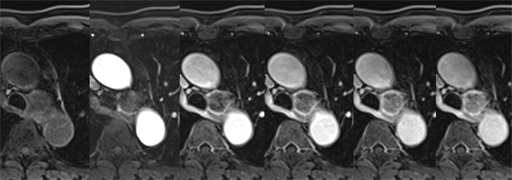

図6 胸部CT 肺野条件 図7 MRI T1WI (in phase)

図7 MRI T1WI (in phase) 図8 MRI T1WI (out of phase)

図8 MRI T1WI (out of phase) 図9 MRI T2WI

図9 MRI T2WI 図10 MRI fat sat T2WI

図10 MRI fat sat T2WI 図11 MRI fat sat T1WI

図11 MRI fat sat T1WI